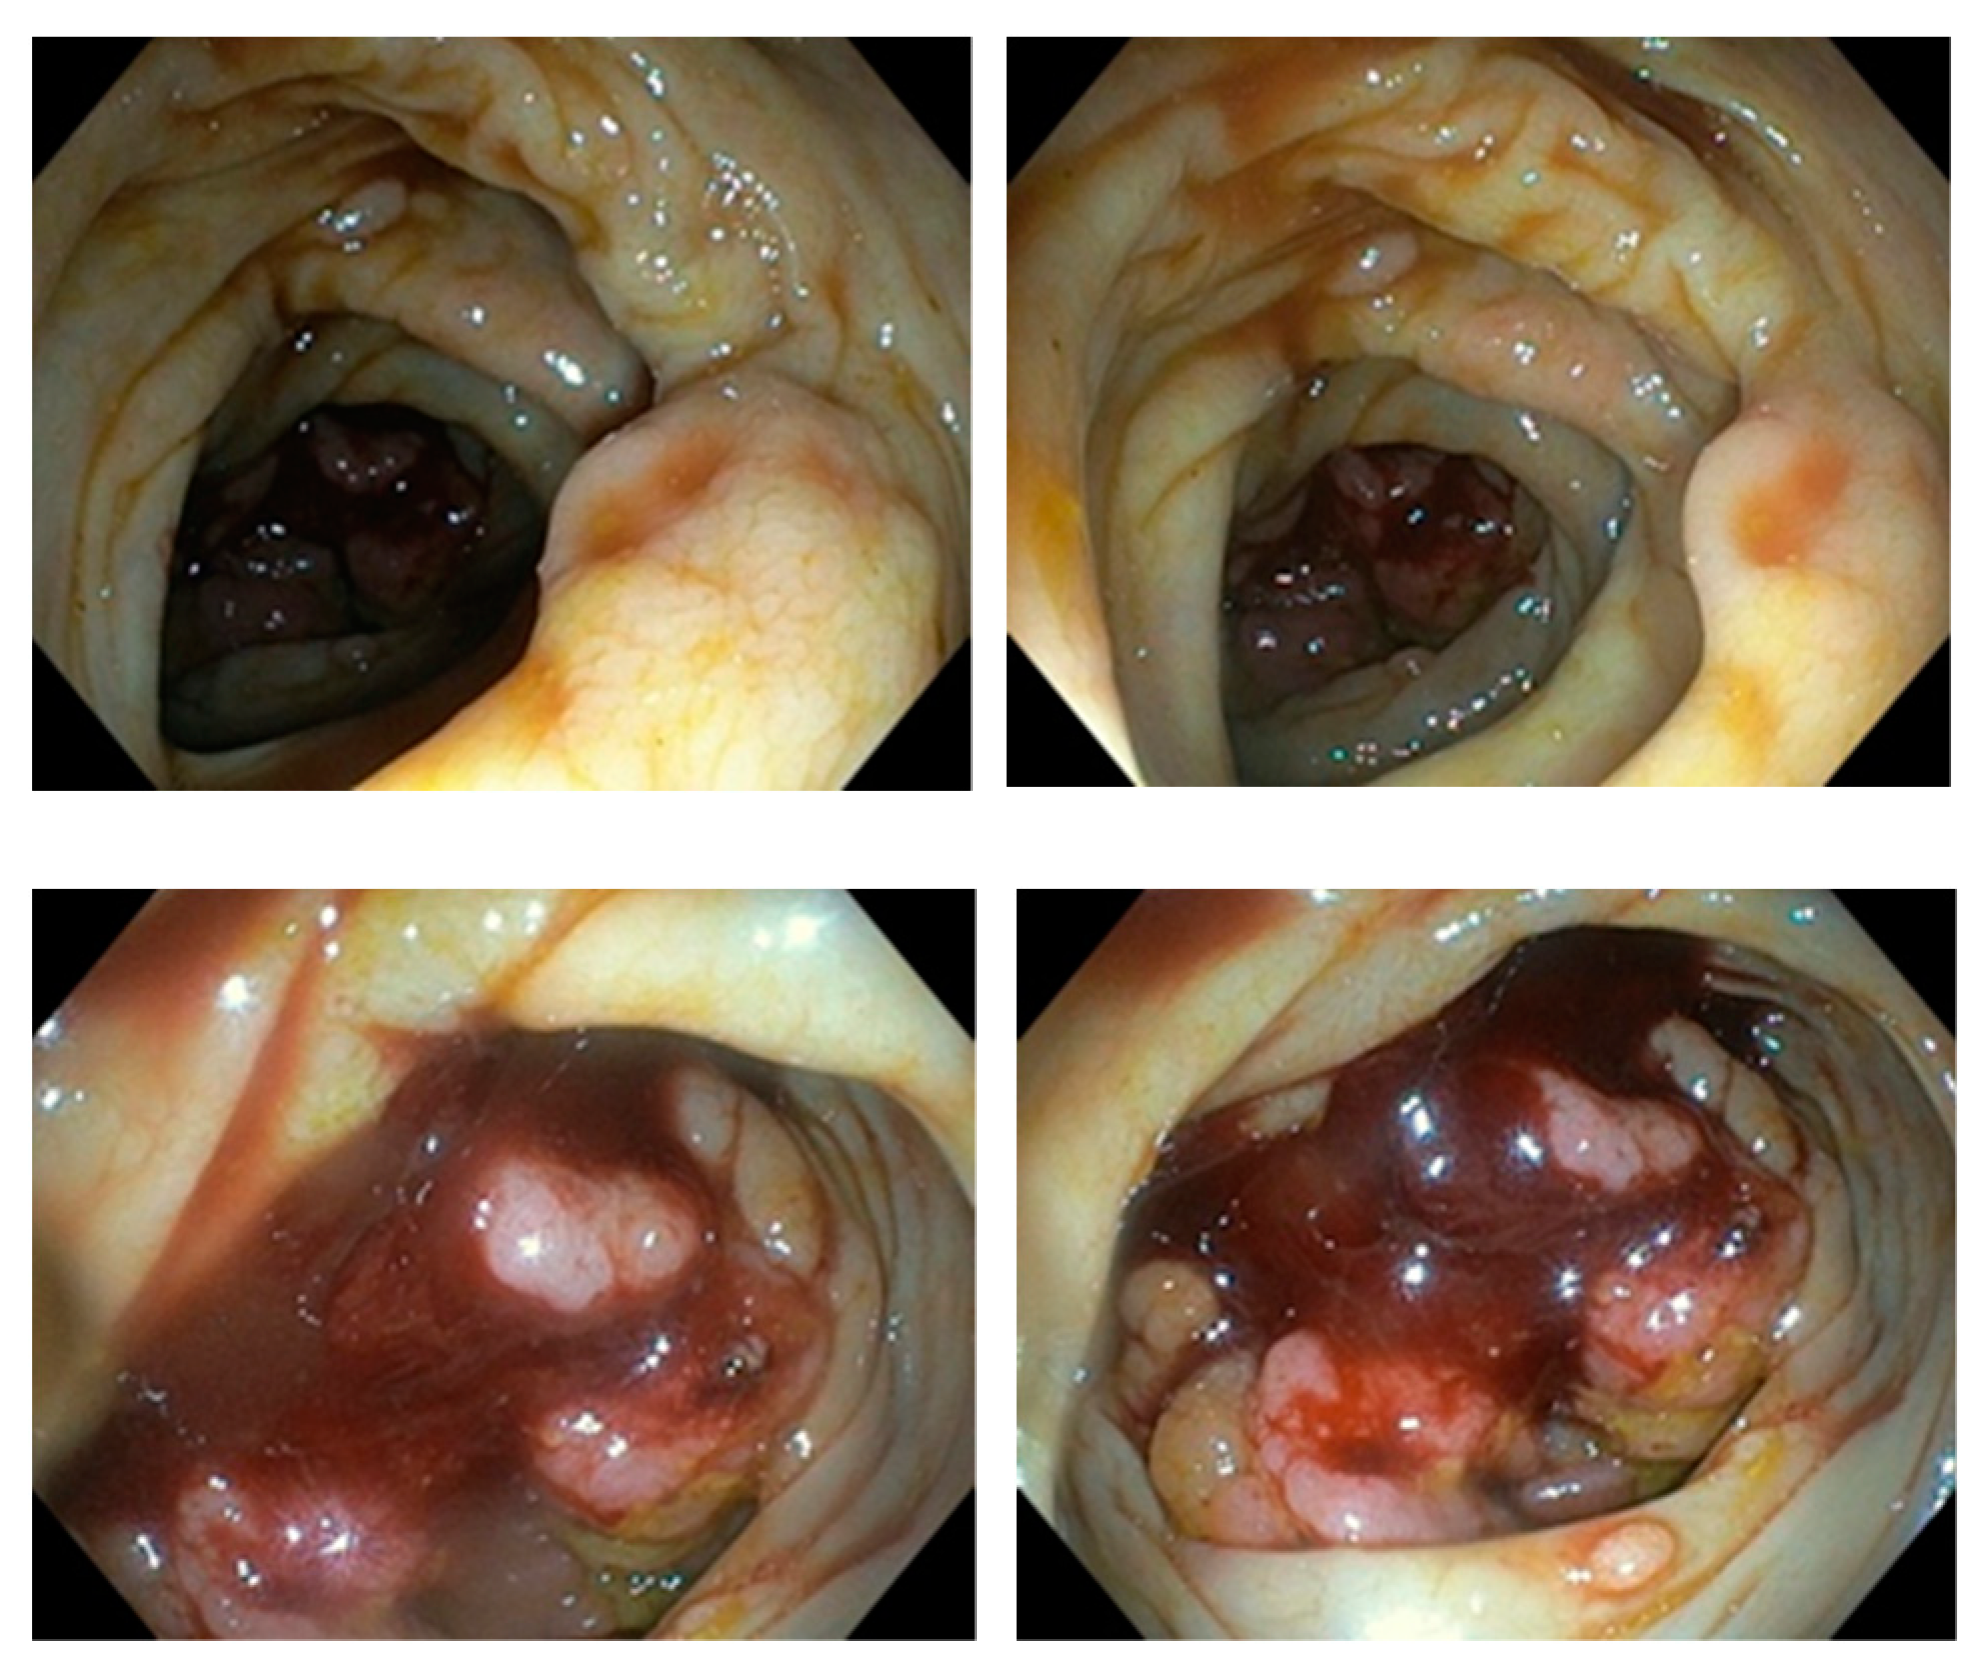

Colonoscopy was incomplete since it was performed only up to hepatic flexure. Further progression to CT-verified cecal infiltration was unsuccessful due to an abnormally long, large intestine (dolichocolon) and malignant rotation of the intestine. NMSE was performed in a retrograde approach in order to reach the ileocecal infiltration. A spiral enteroscope was used to examine the colon because of the abnormal tortuosity of the intestine due to a tumor of the ileocecal segment as well as dolichocolon. A series of light movements of the spiral enteroscope enabled passing through the lumen of the large bowel and reaching a region with circular infiltration that almost completely obstructed the lumen (Figure 3).

Figure 3.

Endoscopic picture of cecal region tumor by Novel Motorised Spiral Enteroscope.